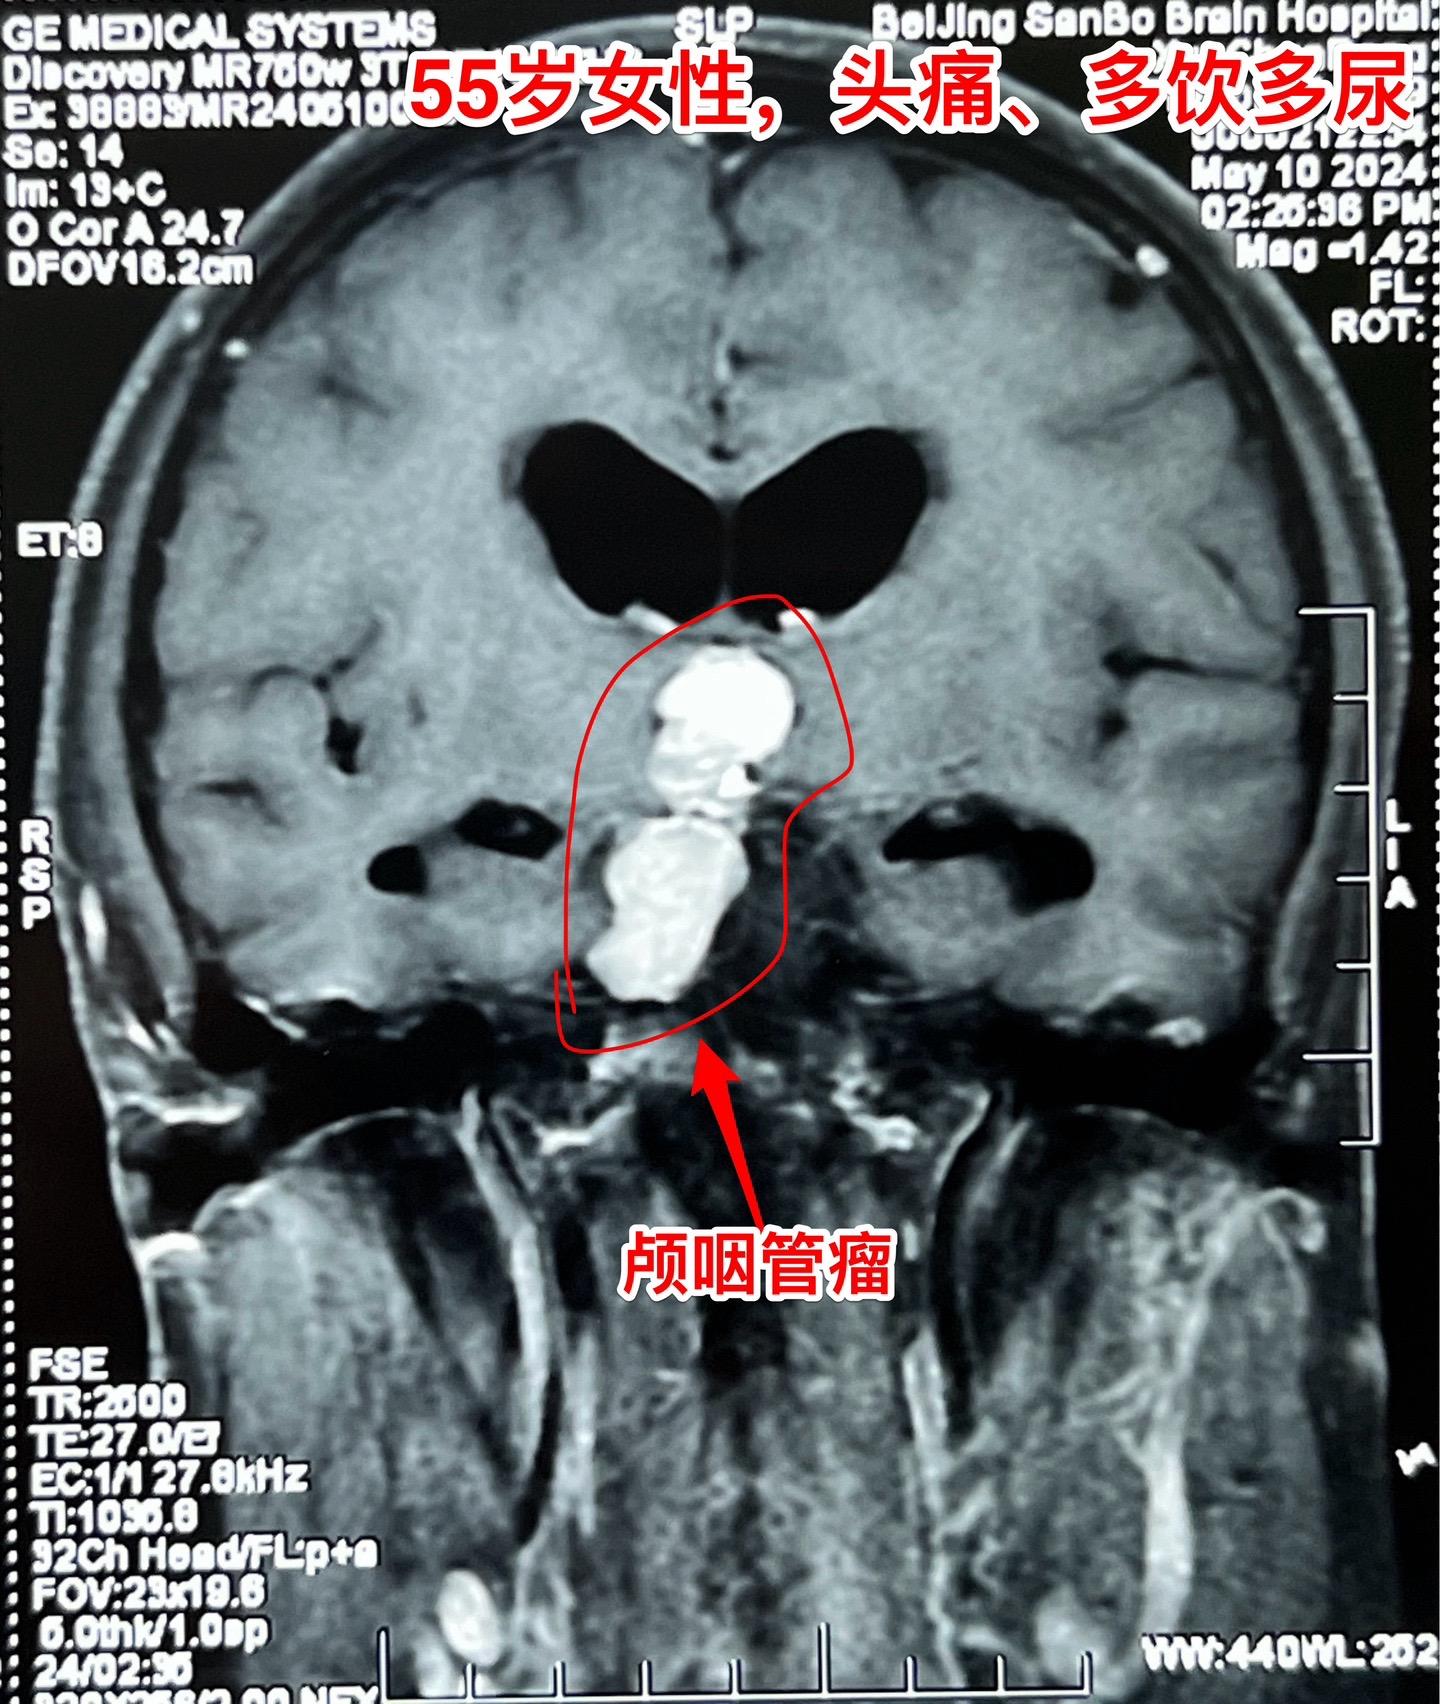

5月16日两个颅咽管瘤手术。五一假期后开展的手术都是颅咽管瘤切除手术。经常一天作两个颅咽管瘤手术!这样的劳动强度有点大! 5.16一天两个颅咽管瘤手术,肿瘤有相似的特征,两个都有大块的钙化斑;都是从垂体柄侵入垂体中;手术方式也相似-经额底纵裂入路。 手术后两个病人都顺利从ICU转移到普通病房。

5月16日两个颅咽管瘤手术。五一假期后开展的手术都是颅咽管瘤切除手术。经常一天作两个颅咽管瘤手术!这样的劳动强度有点大! 5.16一天两个颅咽管瘤手术,肿瘤有相似的特征,两个都有大块的钙化斑;都是从垂体柄侵入垂体中;手术方式也相似-经额底纵裂入路。 手术后两个病人都顺利从ICU转移到普通病房。颅咽管瘤